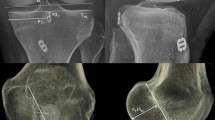

All patients underwent a standardised LDCT 6 weeks post operatively. A Siemens Definition AS+ CT scanner (Siemens Somatom Definition AS+; Siemens Healthcare, Forchheim, Germany) was used. The data was then processed through the clinical software application iterative Metal Artifact Reduction (iMAR) algorithm for metal artifact reduction. Data was imported into Philips 2nd edition software (Philips Medical Systems North America, Shelton, Conn) to create a complete 3D volume reconstruction of each femur (to 10 cm above the femoral condyle) and tibia (to 1 cm below the tibial tubercle). The femoral 3D reconstruction had at least 90% overlap of femoral condyles and then virtual subtraction of the medial femoral condyle at the highest point of the intercondylar notch, leaving the most medial sagittal aspect of lateral femoral condyle with tunnel position on view (Fig. 1). The tibial 3D reconstruction was an axial view, adjusted to view the most superior aspect of the proximal tibia with the femur and patella removed (Fig. 2). The 3D reconstructions were imported into IntelliSpace Patient Archiving and Communication System (IntelliSpace PACS Enterprise; Philips) for measurement.

Tibial tunnel measurement

The tibial tunnel position was assessed using a rectangular reference frame, as has been previously described (Fig. 2) [11, 17]. The posterior border is drawn tangential to the posterior margins of the medial and lateral articular surfaces. The anterior border is drawn parallel to the posterior border, tangential to the anterior margin of the medial articular surface. The medial and lateral borders are drawn tangential to the most medial and lateral articular margins, respectively, perpendicular to the posterior border. Distance F is the mediolateral (ML) dimension of the tibial plateau. Distance G is the AP dimension of the tibial plateau. Point H is the centre of the tibial tunnel. Distance I and Distance J are measured perpendicularly from the medial and anterior borders of the reference frame, respectively. Tibial tunnel position is then defined in the axial plane by calculating ratios I/F and J/G.